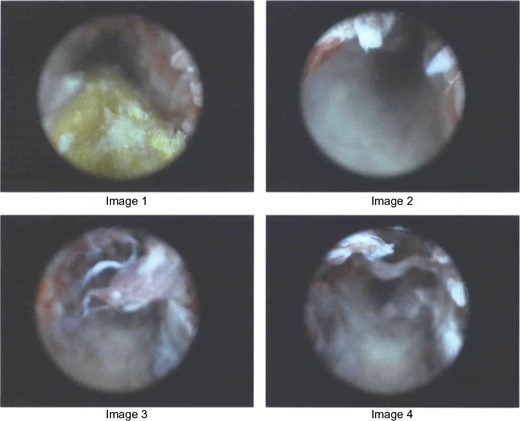

Two months after the initial presentation, the patient returned to the ED for the fourth time complaining of left hip pain. The buttock wound was examined and found to track inward roughly five inches, prompting a CT scan. The imaging showed a linear, partially gas-filled tract starting dorsal to the distal rectum and extending obliquely cephalad and leftward through the obturator internus and iliopsoas musculature (Fig. 1). Soft tissue thickening, mild edema and heterogeneous enhancement were noticed surrounding the tract, but no connection to the rectum or anus was seen.

CT image of a linear, partially gas-filled tract starting dorsal to the distal rectum and extending obliquely cephalad and leftward through the obturator internus and iliopsoas musculature.